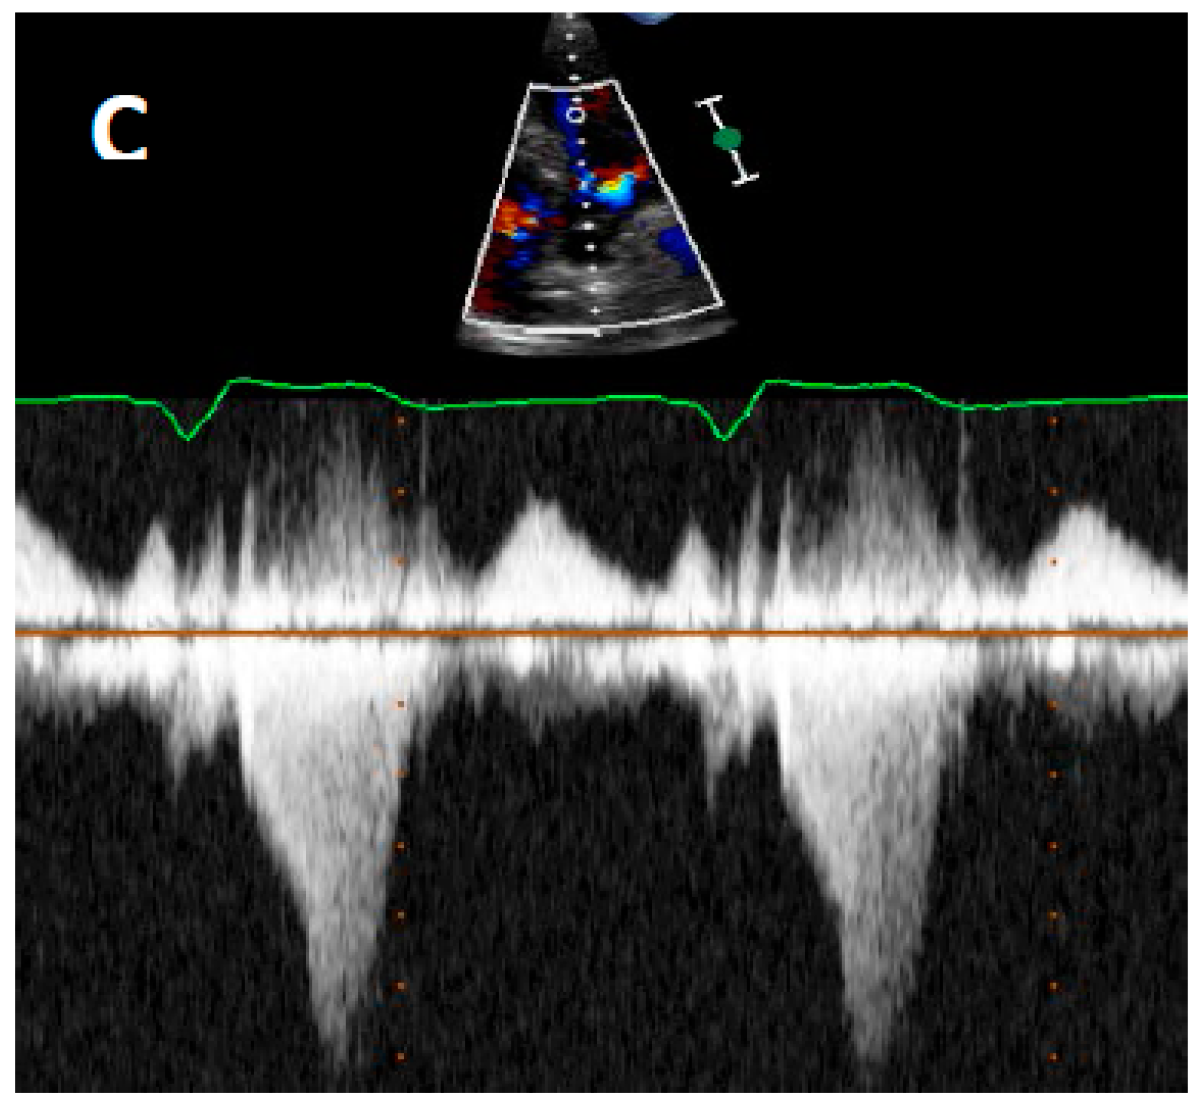

Two factors contribute to LVOTO; hypertrophy of the basal septum and systolic anterior motion (SAM) of the mitral leaflet. In HCM, the mitral valve architecture is abnormal, characterised by leaflet elongation, anterior displacement of the apparatus and papillary muscle abnormalities (Figure 2A). These characteristics make the mitral valve more susceptible to surrounding mechanical forces. As blood flows through the left ventricle in the presence of basal septal hypertrophy, it is directed posteriorly towards the mitral leaflets and then back anteriorly towards the LVOT [34,35]. When blood flows back towards the LVOT, it drags the mitral apparatus, resulting in an anterior motion of the leaflets. This SAM of the mitral leaflets is further reinforced by the Venturi effect produced by the higher velocity of blood flow induced by a narrower LVOT. As the mitral leaflets move anteriorly, they are directed towards the hypertrophied septum, touching the septum in severe instances.

Figure 2.

(A) Schematic demonstrating how left ventricular hypertrophy (LVH) with unfavourable mitral valve anatomy may result in obstruction of the left ventricular outflow tract. Echocardiography allows high quality imaging of the left ventricular outflow tract due to systolic anterior motion of the anterior mitral valve leaflet; (B) Abnormal motion of the mitral valve is well demonstrated on M-mode echocardiography. This may result in high velocities through the LVOT seen on continuous wave Doppler imaging as seen in (C). LA—Left atrium. MV—Mitral valve. LV—Left ventricle. LVOT—Left ventricular outflow tract, LVH—Left ventricular hypertrophy, Ao—Aort.

Echocardiography has transformed diagnostic testing in cardiology. In 1969, Moreyra et al. pioneered the use of echocardiography in diagnosing HCM [21]. The idea of SAM of the mitral leaflet in systole contributing or causing LVOT obstruction was first postulated by Bjork in 1965 at a symposium in London [20]. Due to the lack of supporting evidence at the time, this view was initially unpopular. However, this changed as subsequent angiographic contrast studies demonstrated a characteristic SAM of the mitral leaflet in systole leading to LVOT obstruction [37,38,39]. In 1969, Shah et al. confirmed the finding of SAM of the mitral leaflet using echocardiography and found it to be distinctive of HCM [22] (Figure 2B). The introduction of 2D echocardiography in 1972 allowed direct visualisation of the aortic valve and LVOT, allowing the non-invasive distinction of HCM and aortic stenosis [23].

Two-dimensional (2D) echocardiography has long been the mainstay initial modality of choice in HCM diagnosis. It is used to outline cardiac structures and assess valvular and cardiac function. Doppler echocardiography at rest and during Valsalva manoeuvre is recommended to detect evidence of resting or latent LVOTO (Figure 2C). Left ventricular ejection fracture (LVEF) is usually normal or supra-normal in HCM, while the internal cavity left ventricular (LV) systolic dimensions are often small. As such, myocardial strain may be a better measure of systolic function than LVEF in HCM. Myocardial strain may be measured with Doppler myocardial strain imaging and 2D speckle-tracking technology [40]. Indeed, reduced LV myocardial strain in HCM has been shown to be associated with NSVT, appropriate ICD discharges and cardiac death [41,42,43]. Echocardiography provides detailed assessment of diastolic function, which is often abnormal in HCM.